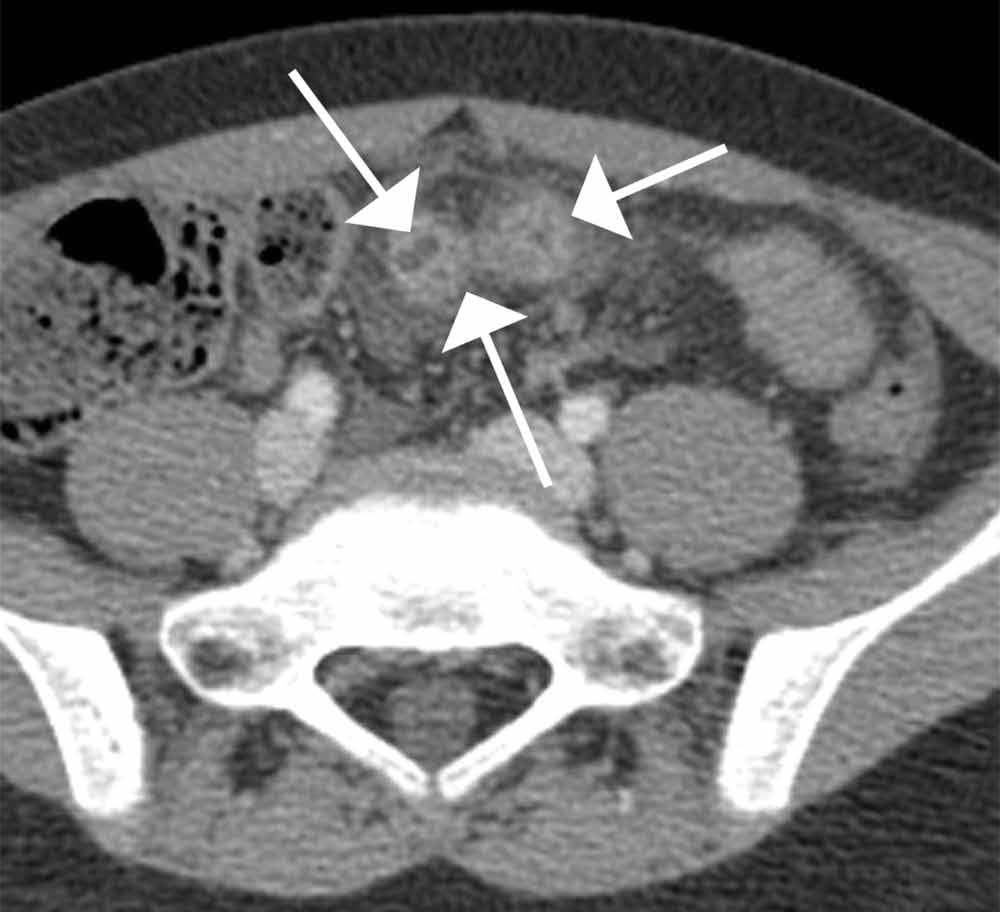

Computed tomography revealed a blind-ending tubular structure (white arrows, Figure 1c) deep to the umbilicus arising inferiorly from a loop of distal ileum with surrounding fat stranding (Figure 1d). The fluid-containing tubular structure demonstrates marked enhancement of the mucosa. These findings are most consistent with Meckel’s diverticulitis.

Figure 1C | Figure 1D |